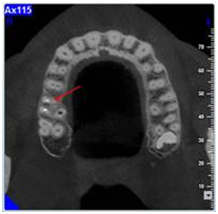

The treatment procedure consisted on the removal of the crown with the aid of a crown removal kit; ultrasonic tips were used for the removal of the metallic post, and the search for the entrance of the second mesial canal was conducted with the use of binoculars. While searching for the MB2 a perforation in the pulp chamber floor was performed. Decision was made to obturate the perforation with MTA and to postpone the session until a CBCT is done. While studying the CBCT, the cuts in the three planes (axial, sagittal and frontal cuts) showed a clearly not obturated canal in the mesial root in direct relation with the lesion (Figure 3). A new search for the MB2 entrance was conducted and finally the MB2 entrance is found. Endodontic therapy was done and two separated mesiobuccal canals where completely cleaned and obturated. A peri-apical radiograph was done five month later showing the complete cicatrisation of the lesion (Figure 4).

Figure 3 CBCT exam; the axial cuts show the entrance of the MB2, the sagittal and frontal cuts show an entire MB2 canal with the radiolucency attached to its apical part.